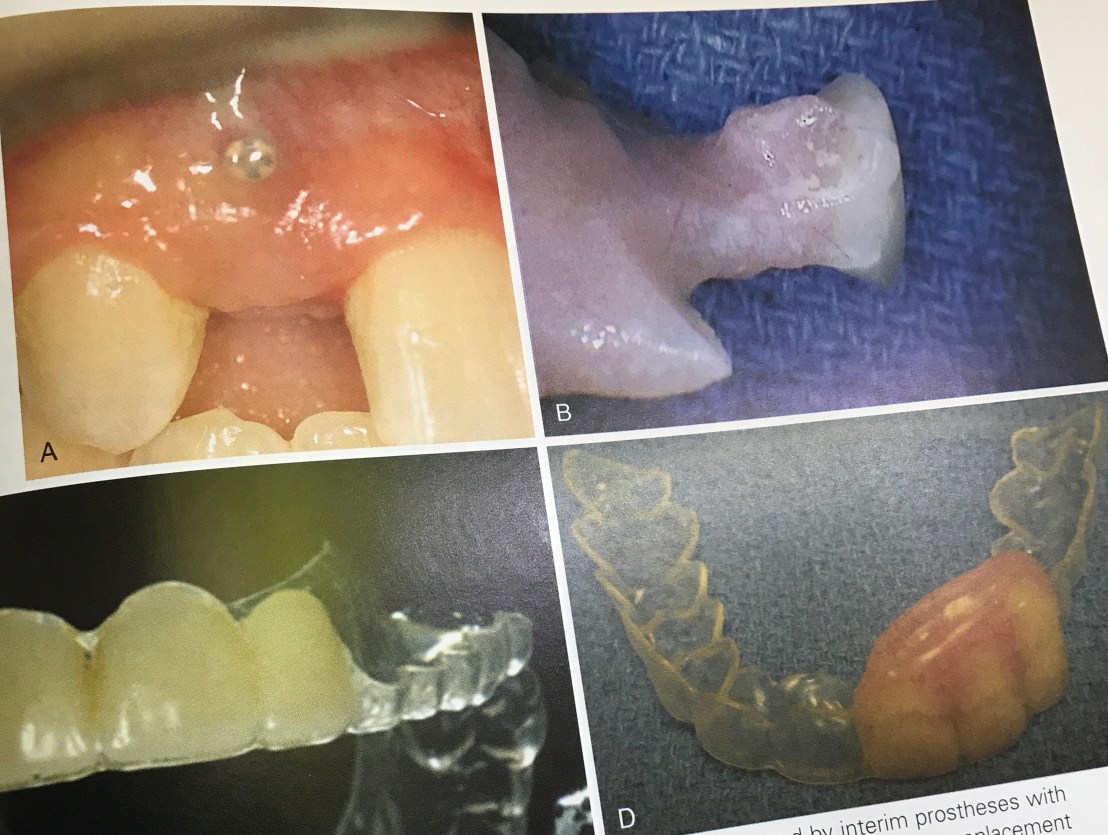

Prosthesis ในรูป C และ D คือ Essix appliance ใช้การได้ retention จากฟันเหมือน tray ฟอกสีฟัน เนื่องจากเป็น Temporary tooth support ซึ่งไม่ได้อาศัย tissue support จึงขจัดปัญหา Excessive pressure บนสัน ridge ที่ถูก augment ได้